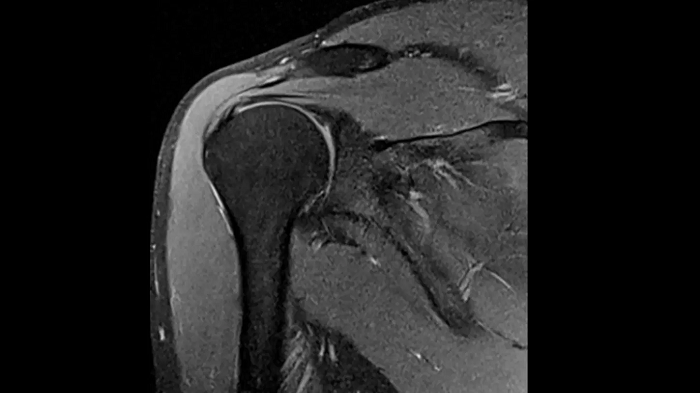

Shoulder

PD TSE Fat Sat with Deep Resolve and Simultaneous Multi-Slice

Exceptional fat suppression and performance for the shoulder’s clear imaging. Integrating the Deep Resolve’s power with the proven Simultaneous Multi-Slice technique.

SMS 2 | Deep Resolve Gain & Sharp

0.4 x 0.4 x 3.0 mm2

TA 3:20 minutes

MAC-ID: 7aaaa0213. Image Credit: Siemens Healthineers

T1 TSE with Deep Resolve and Simultaneous Multi-Slice

Outstanding T1 imaging of the shoulder using MAGNETOM Free.Star. Integrating the Deep Resolve’s power with the proven Simultaneous Multi-Slice technique.

SMS 2 | Deep Resolve Gain & Sharp

0.4 x 0.4 x 3.0 mm2

TA 3:37 minutes

MAC-ID: 7aaaa0213. Image Credit: Siemens Healthineers